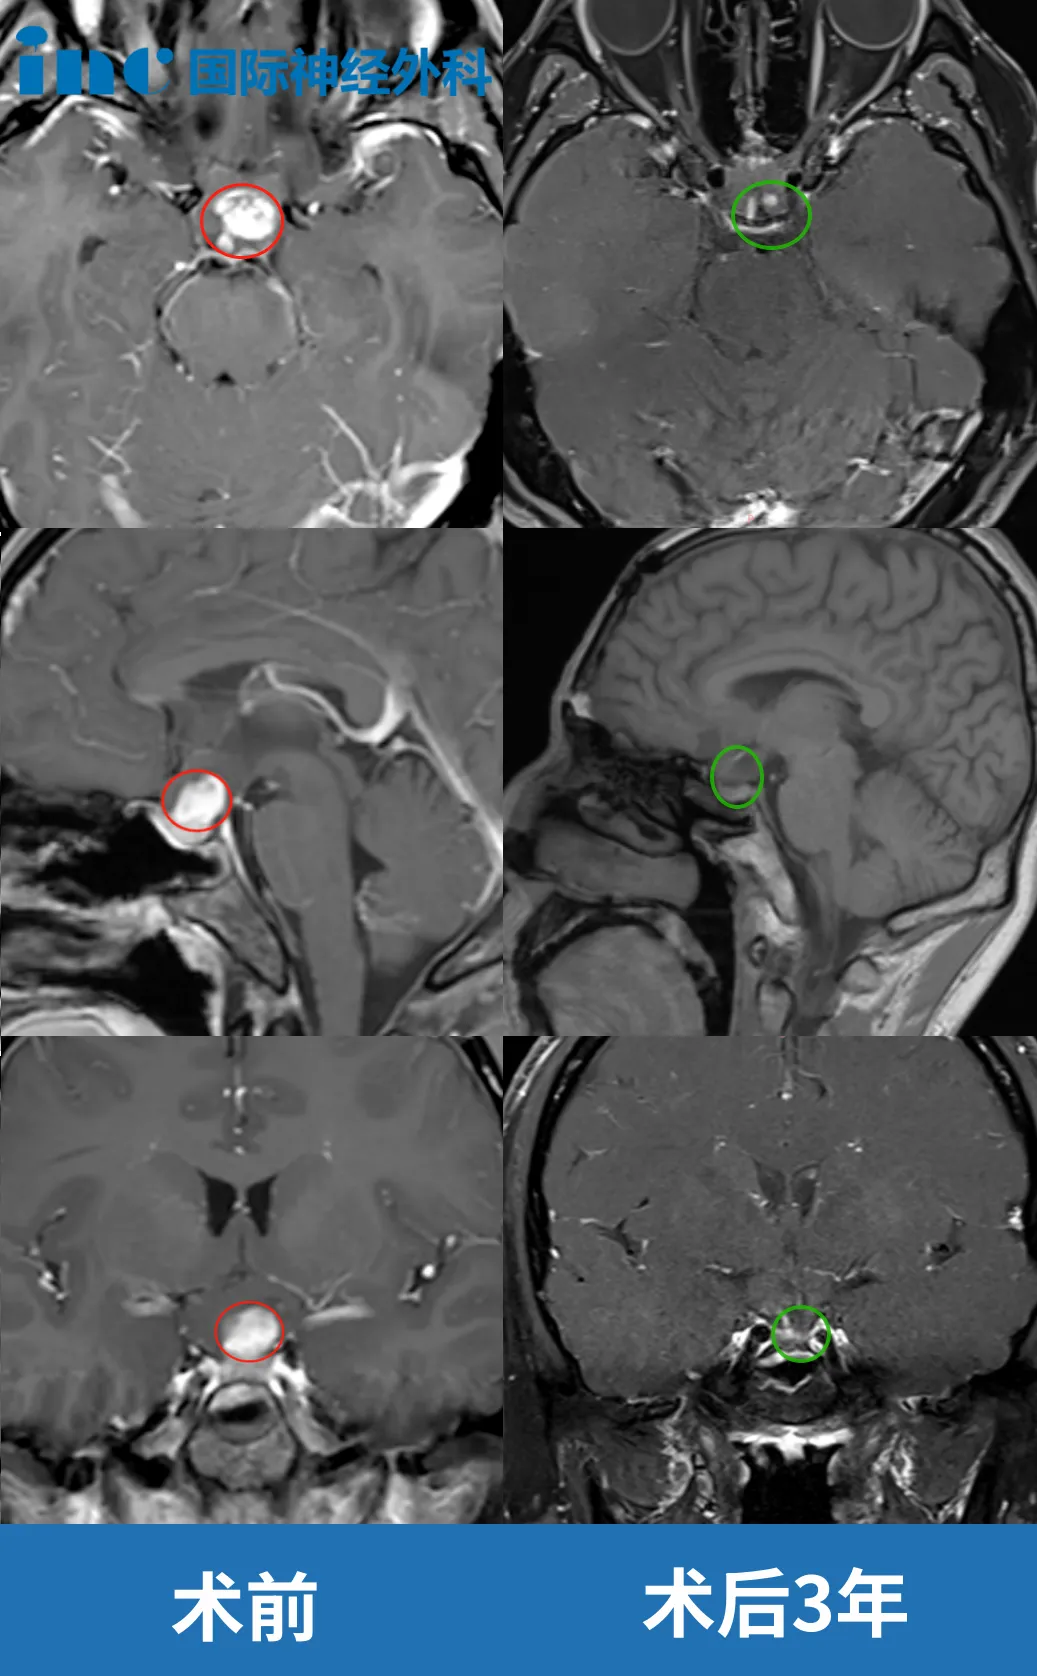

6岁男孩视神经-毛细胞星形细胞瘤

患者情况:2022年6月9岁的悦悦出现头疼、视力下降,检查提示鞍上肿瘤,考虑“颅咽管瘤”,7月予以行鞍区肿块切除术,因肿瘤位于视神经,为保留患者视力仅活检手术,术后病理报告提示鞍区低级别胶质瘤,考虑毛细胞星型细胞瘤WHO1级。而毛细胞星型细胞瘤只要达到安全切除,孩子可以长期生存。然而手术风险很大,稍有不慎便会造成失明的严重后果......踌躇两难之际,悦悦父母得知了“巴教授来华“的消息。“只要巴教授说可以做手术,我们就不做化疗了”,悦悦父母在找到巴教授之后重拾信心。

治疗过程:后求诊于INC国际神经外科教授,在巴教授主刀下完成了保神经、近全切的手术(切除率达到了95%以上),手术结束后一个小时左右苏醒。当天就转到普通病房,术后巴教授去病房查房,孩子对答如流,视力得以保留。悦悦父母终于可以放下心来,孩子一切都很好,可爱活泼、充满神采,回归校园。